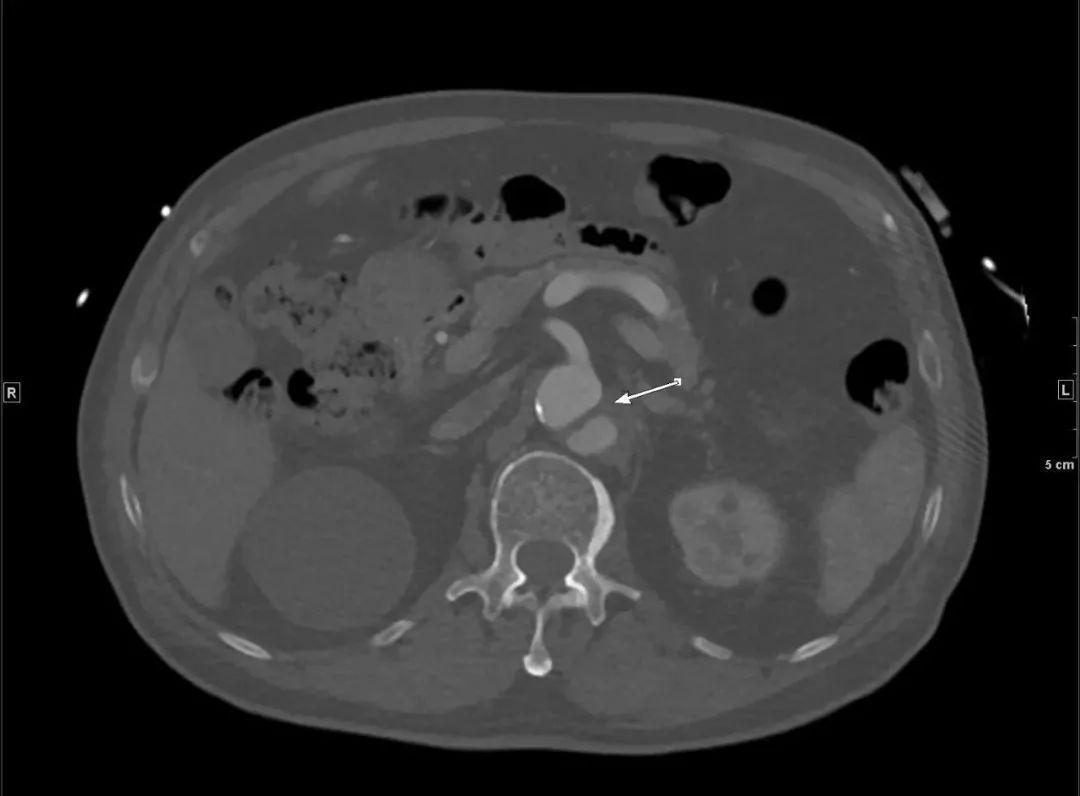

还好,那一下午人不不多,很快开申请单、登记、预约,一小时后做了胸腹盆增强CTA,当看到增强图像时,让我们倒吸一口凉气,约L1椎体水平至左侧髂总动脉夹层。患者紧急住院。

腹主动脉CTA腹腔干水平(骨窗) 左侧髂总动脉(骨窗)